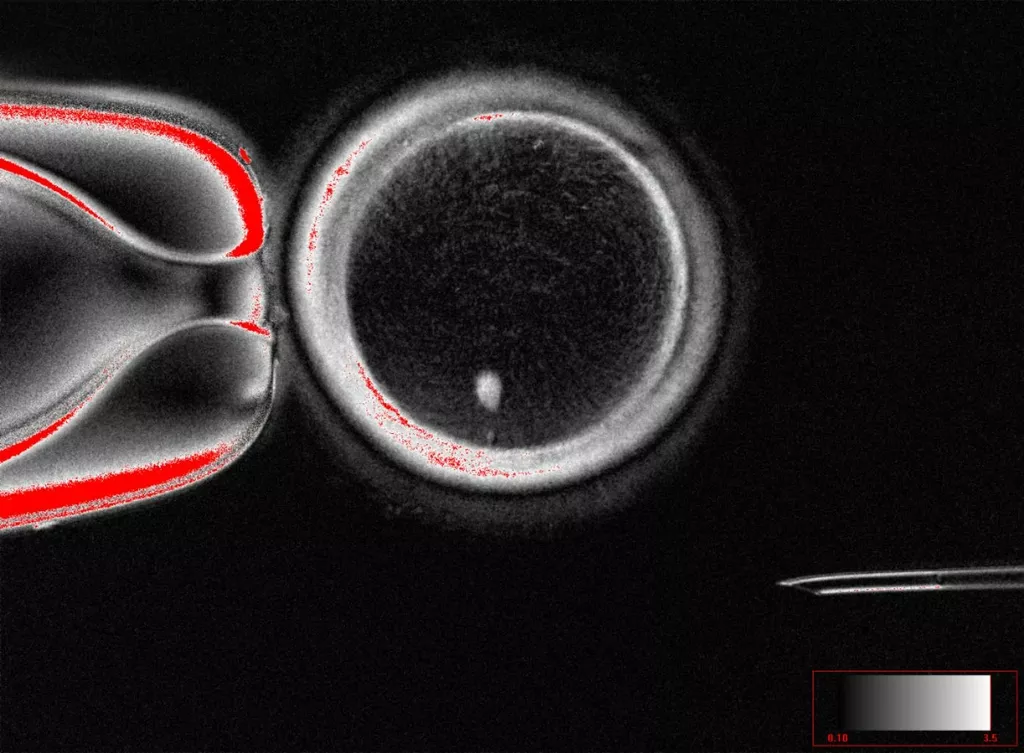

研究團隊使用的方法,是將屬於體細胞的皮膚細胞細胞核,移植到已移除細胞核的生殖細胞卵子或卵母細胞中,在被蛋白激酶抑制劑roscovitine改造過的卵子細胞質刺激下,會誘使植入的皮膚細胞核分裂、丟棄一半染色體,最終形成一顆僅擁有23條染色體的卵子。

研究團隊表示,已透過同一方法成功培養82顆具功能性的卵子,並透過體外受精技術與精子進行受精,但只有9%的胚胎發展到第6天,也就是可植入子宮的囊胚階段,研究團隊也未持續培養成為囊胚的胚胎。